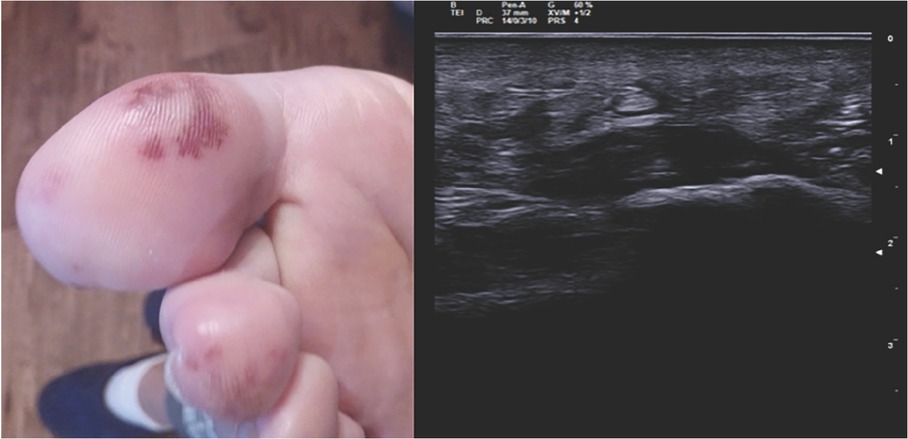

A 31-year-old woman was admitted becayse of relapse of seronegative enthesoarthritis. The patient complained of arthralgias at metatarsophalangeal joints (MTP) bilaterally and pain on the plantar surface of the feet for 1 year, which showed a partial response to anti-inflammatory drugs. After 2 months from the onset of the articular symptoms, the patient developed purpuric lesions on the plantar surface bilaterally (Figure 1, left). No improvement happened after being treated with prednisone 50mg/d (rapidly tapered). Blood tests showed increased levels of inflammatory indices (CRP 12 mg/dL, and ESR 22 mm/h), negative for rheumatoid factor (RF), and anticitrullinated peptide autoantibodies (aCCP). Musculoskeletal ultrasound showed a bilateral plantar fascia edema (compatible with plantar fasciitis) and synovitis of right metacarpophalangeal joints (MTP) (Figure 1, right). Diagnosis of seronegative “early arthritis” was made, and the patient started treatment with methylprednisolone 4 mg/d and methotrexate (MTX) 7.5 mg/week, without improvement. The purpuric lesions and arthralgias worsened with onset of moderate exertional dyspnea and episodes of palpitations. No swollen joints was found during physical examination but diffuse MTP tenderness and pain at pressure at the plantar fascia bilaterally. Purpuric lesions were found on the plantar surface bilaterally. No heart murmur was detected. She underwent a blood test with evidence of increased inflammatory indices (ESR 52 mm/h, CRP 17 mg/dL), negative for antinuclear autoantibodies (ANA), extractable nuclear antigens (ENA), anti-dsDNA, anti-neutrophil cytoplasmic antibodies, antiphospholipid antibodies, cryoglobulins, and serology for HBV, HCV, tuberculosis, and syphilis. A nail videocapillaroscopy was in normal pattern. To better characterize the dyspnea, a TTE was performed which revealed a pedunculated mass in the left atrium.

Figure 1 Purpuric lesions on the plantar side of the right foot (left). Echographic image of plantar fascia edema of the left foot (transverse section) (right).

Purpuric lesions on the plantar side of the right foot (left). Echographic image of plantar fascia edema of the left foot (transverse section) (right).